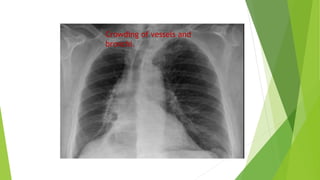

† Vascular signs. In partial collapse, crowding of vessels may be

seen.

Crowding of vessels and

bronchi.

Direct signs These include: †Increased opacification in the area of atelectasis. Air bronchograms are normally a feature of consolidation but may also b present in lobar collapse. † Displacement of fissures. This occurs with large degree of collapse. † Loss of aeration. If the collapsed lung is adjacent to the mediastinum or diaphragm, then loss of definition of these structures indicates loss of aeration (the silhouette sign). † Vascular signs. In partial collapse, crowding of vessels may be seen.

Crowding of vesselsand bronchi.